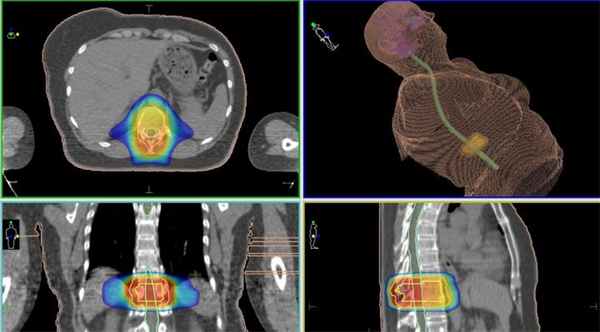

Метастаз в позвоночник, лечение без операции на КиберНоже в Киеве — цифровой план лечения, на котором указано размещение метастаза (к нему будет подведена разовая высокая доза ионизирующего облучения), здоровых тканей и критически важных структур (они полностью защищены от облучения — синим контуром задана «холодная зона», через который не пройдет ни один из пучков излучения)

Спинальный метастаз, высокточная лучевая терапия — цифровой план лечения с указанеим распределения доз для опухолевой зоны и здоровых тканей, а также «холодных зон», защищаемых от облучения)